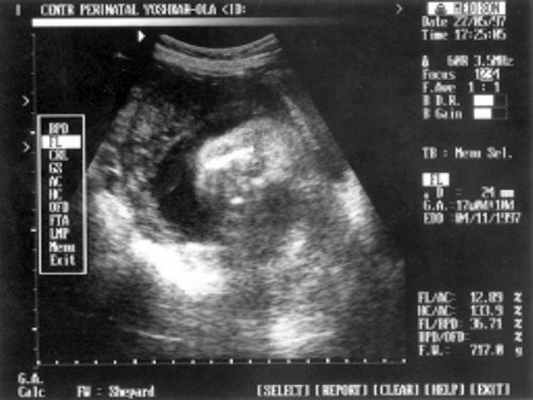

Беременная П., направлена на ультразвуковое исследование плода на сроке 24 нед. беременности. Настоящая беременность - 2-я; 1-я закончилась медицинским абортом на сроке 9 нед. без осложнений. Соматический и наследственный анамнезы не отягощены. Эхографическое исследование плода проводилось с помощью ультразвукового сканера "SonoRex" , оснащенного трансабдоминальным датчиком 3,5 МГц.

При ультразвуковом исследовании обнаружено: 1 живой плод в головном предлежании.

Данные фетометрии:

- (бипатериальный размер головы - от виска до виска) = 65 мм - 26 нед.,

- ОкГ (окружность головы) = 244 - 26 нед. + 3 дня.

- МРМ (межполушарный размер мозжечка) = 25,6 мм - 23,5-24 нед. (рис. 1)